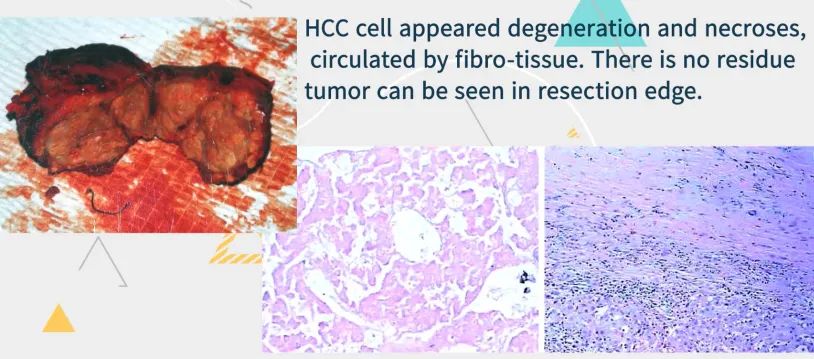

患者,女,59岁,肝细胞肝癌,5-10年前有子宫内膜癌、乳癌。

患者经过三次cTACE,随访3年,肿瘤持续缩小,无强化。

术前TACE,利于肿瘤切除。

术后病理证实无存活肿瘤,随访十一年健康生存。